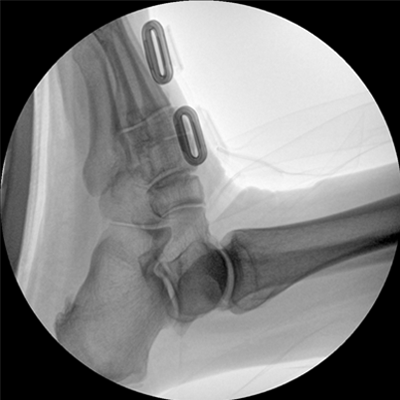

四維電動(dòng)運(yùn)動(dòng)控制,平滑定位,使得復(fù)雜角度快速實(shí)現(xiàn)。

專(zhuān)業(yè)的圖像處理系統(tǒng),為您提供高分辨率、高灰階圖像。